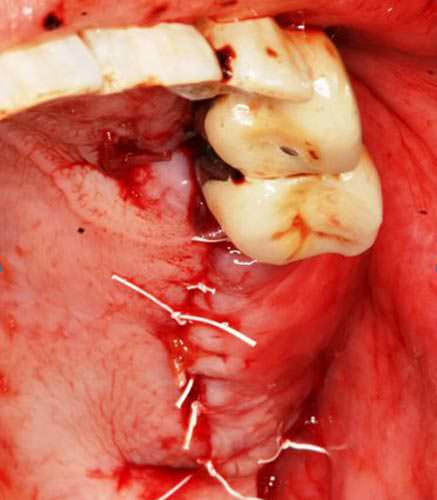

Finalmente se procedió a la aproximación de los colgajos y al cierre mediante sutura 4-0 no absorbible (PTFE) monofilamento (Fig 14).

Fig.14